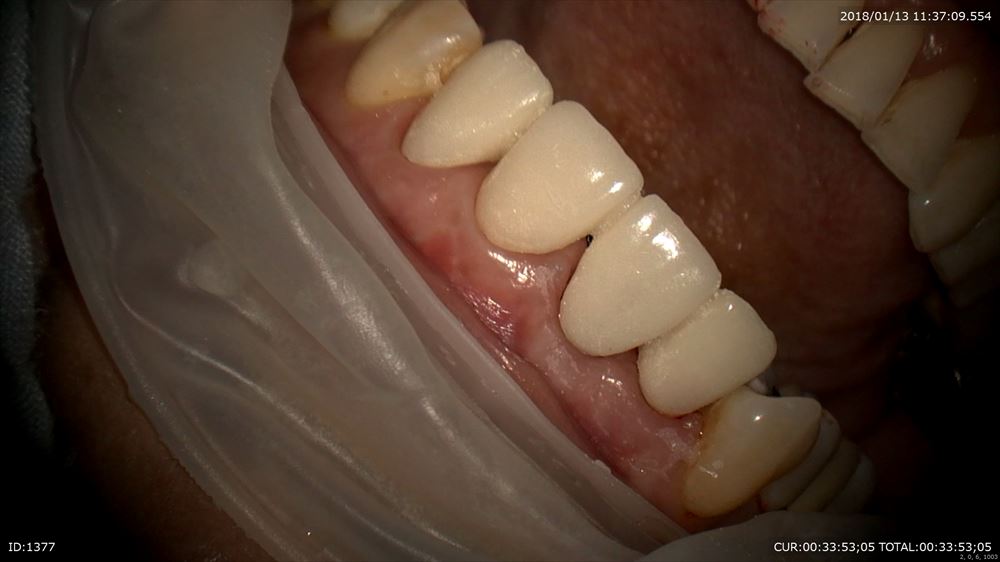

右上1番のインプラント歯茎の形態を仮歯で作ります。

マイクロスコープ治療で仮歯を調整。

エマージェンスプロファイルを調整。

仮歯完成!!インプラントの淵が見えなくなりました。あー緊張した。ここまで1年。患者さま喜んで頂けました。